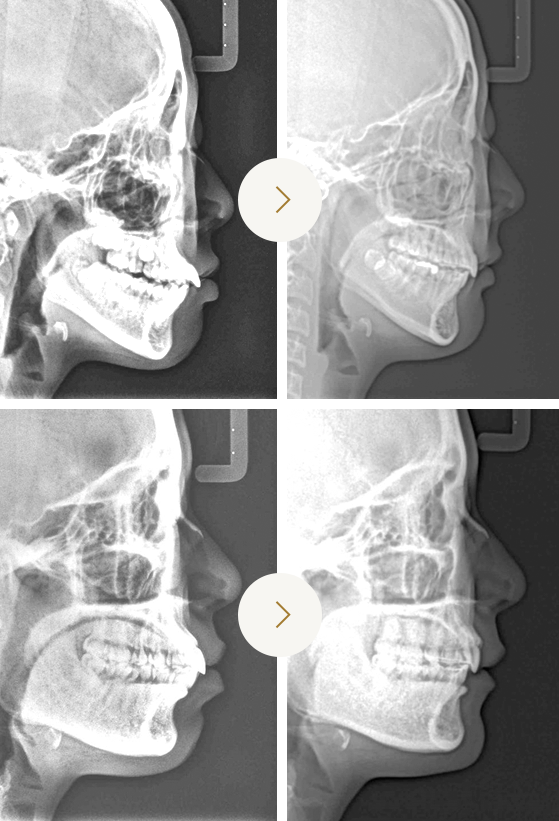

Before & After

발치 돌출입 교정을 통한 입술선의

변화만으로도 인상이 달라져 보일 수 있습니다.

발치 돌출입 교정치료 이후

옆모습 엑스레이 사진 변화입니다.